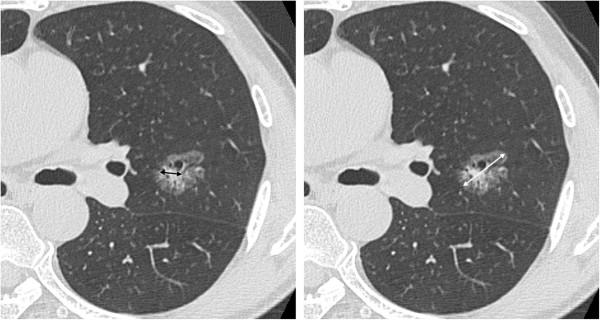

The ratio of the maximum diameter of consolidation to the maximum tumor diameter (C/T ratio) on thin-section computed tomography (TSCT) and the maximum standardized uptake value (SUVmax) on 18 F-fluorodeoxyglucose positron emission tomography/computed tomography (PET/CT) are often used as preoperative independent variables to evaluate the invasiveness of lung adenocarcinoma. We investigated the associations between these independent variables and pathologic invasiveness in pulmonary adenocarcinomas.

We evaluated a total of 163 primary lung adenocarcinomas in 148 patients (93 males and 55 females; age range: 34 to 84 years). Using multivariate logistic regression analysis, SUVmax and the C/T ratio were significantly associated with tumor invasiveness (odds ratio [OR] = 1.227; p = 0.025 and OR = 1.019; p = 0.008, respectively). Tumor size was not associated with invasiveness (OR = 1.003; p = 0.925). For solid type adenocarcinomas, only SUVmax was significantly associated with invasiveness (OR = 1.558; p = 0.003). For subsolid type adenocarcinomas, only the C/T ratio was significantly associated with invasiveness (OR = 1.030; p = 0.009).

Both the C/T ratio and the SUVmax are significantly correlated with pathologic invasiveness in patients with small lung adenocarcinomas, while there was a difference between the 2 evaluations. Solid type adenocarcinomas with SUVmax values of ≥ 4.4 and subsolid type adenocarcinomas with C/T ratio ≥ 53% were so highly invasive.